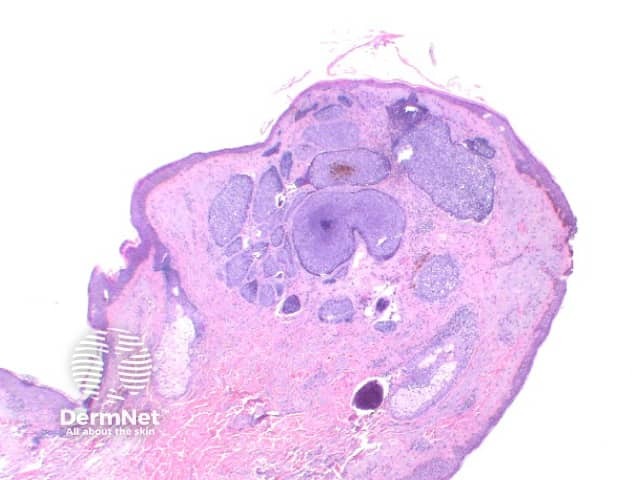

The key feature of basal cell carcinoma at low power magnification is of a basaloid epithelial tumour arising from the epidermis (figure 1). The basaloid epithelium typically forms a palisade with a cleft forming from the adjacent tumour stroma (figure 2). Centrally the nuclei become crowded with scattered mitotic figures and necrotic bodies evident (figure 3). A useful distinguishing feature from other basaloid cutaneous tumours is the presence of a mucinous stroma (figure 4). Some tumours may also show foci of regression, seen as areas of eosinophilic stroma with lack of basaloid nests.

Figure 1

Nodular BCC: The tumour forms a solid tumour nodule or nodules which may extend into subcutaneous tissues. Cartilaginous invasion is unusual (figure 1).